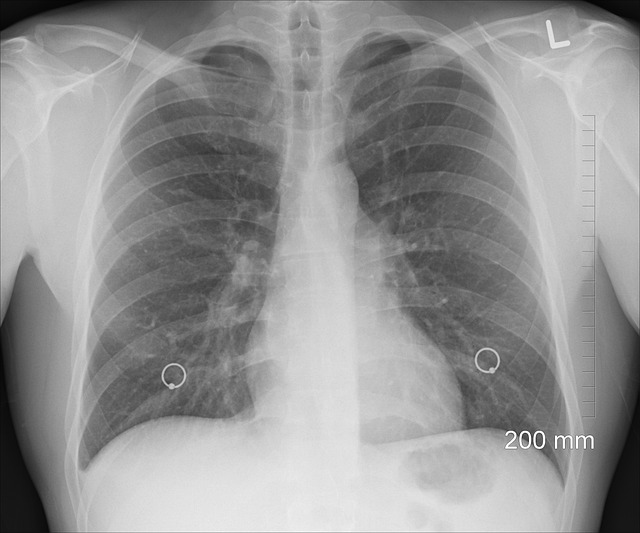

폐렴(Pneumonia)은 세균, 바이러스, 곰팡이 등의 감염으로 인해 폐에 염증이 발생하는 질환으로, 고열, 기침, 가래, 호흡곤란, 흉통 등의 증상을 동반합니다. 일반적인 감기나 독감과 유사한 증상으로 시작될 수 있지만, 감염이 폐 깊숙이 퍼지면 호흡 곤란과 전신 쇠약감을 유발하며, 심한 경우 패혈증이나 급성 호흡 부전으로 이어질 수 있습니다. 특히 노인, 영유아, 만성 질환자, 면역력이 약한 사람들에게서 위험성이 높으며, 적절한 치료를 받지 않으면 생명을 위협할 수 있는 심각한 질환입니다. 이번 글에서는 폐렴의 원인, 증상, 치료법에 대해 자세히 알아보겠습니다.

증상은 병원체의 종류, 환자의 건강 상태, 면역력 등에 따라 다양하게 나타날 수 있습니다. 하지만 일반적으로 고열, 기침, 가래, 호흡곤란, 흉통 등의 증상이 주요하게 나타납니다. 폐렴의 대표적인 증상 중 하나는 발열과 오한입니다. 세균성 폐렴의 경우 갑작스럽게 38~40℃ 이상의 고열이 발생하며, 오한을 동반하는 경우가 많습니다. 반면, 바이러스성 폐렴은 고열이 나타나지 않을 수도 있으며, 미열과 전신 권태감이 지속될 가능성이 큽니다. 기침과 가래도 폐렴의 주요 증상입니다. 초기에는 마른기침이 나타날 수 있지만, 시간이 지나면서 점점 가래가 포함된 기침으로 변할 수 있습니다. 가래의 색깔은 원인 병원체에 따라 다를 수 있으며, 세균 감염일 경우 누런색 또는 녹색 가래가 동반되는 경우가 많고, 폐렴구균 감염일 경우 갈색 또는 녹슨 색깔의 가래가 나올 수도 있습니다. 바이러스성 폐렴은 상대적으로 가래가 적을 수 있지만, 기침이 오래 지속될 가능성이 높습니다. 호흡곤란과 흉통도 폐렴 환자들에게서 흔히 나타나는 증상입니다. 폐에 염증이 심해지면 산소 교환이 원활하지 않아 숨쉬기가 어려워지며, 가벼운 활동에도 숨이 찰 수 있습니다. 흉막(폐를 둘러싸고 있는 막)에 염증이 생기면 숨을 들이마실 때 가슴이 찌르는 듯한 통증(늑막통)이 발생할 수 있으며, 이는 심한 경우 숨을 깊게 들이마시거나 기침을 할 때 더욱 악화될 수 있습니다. 일반적인 감기나 독감과 다르게, 폐렴 환자는 전신 쇠약감, 피로, 식욕 부진 등의 증상이 뚜렷하게 나타나는 경우가 많습니다. 노인의 경우 폐렴이 발생하면 전형적인 호흡기 증상이 나타나지 않을 수도 있으며, 대신 혼돈(인지 장애), 의식 저하, 식욕 감소, 탈수 등의 비특이적인 증상이 먼저 나타날 수 있습니다. 폐렴은 방치할 경우 패혈증, 급성 호흡 부전, 폐농양, 흉막염 등의 심각한 합병증을 유발할 수 있으므로, 증상이 나타날 경우 조기에 진료를 받는 것이 중요합니다.